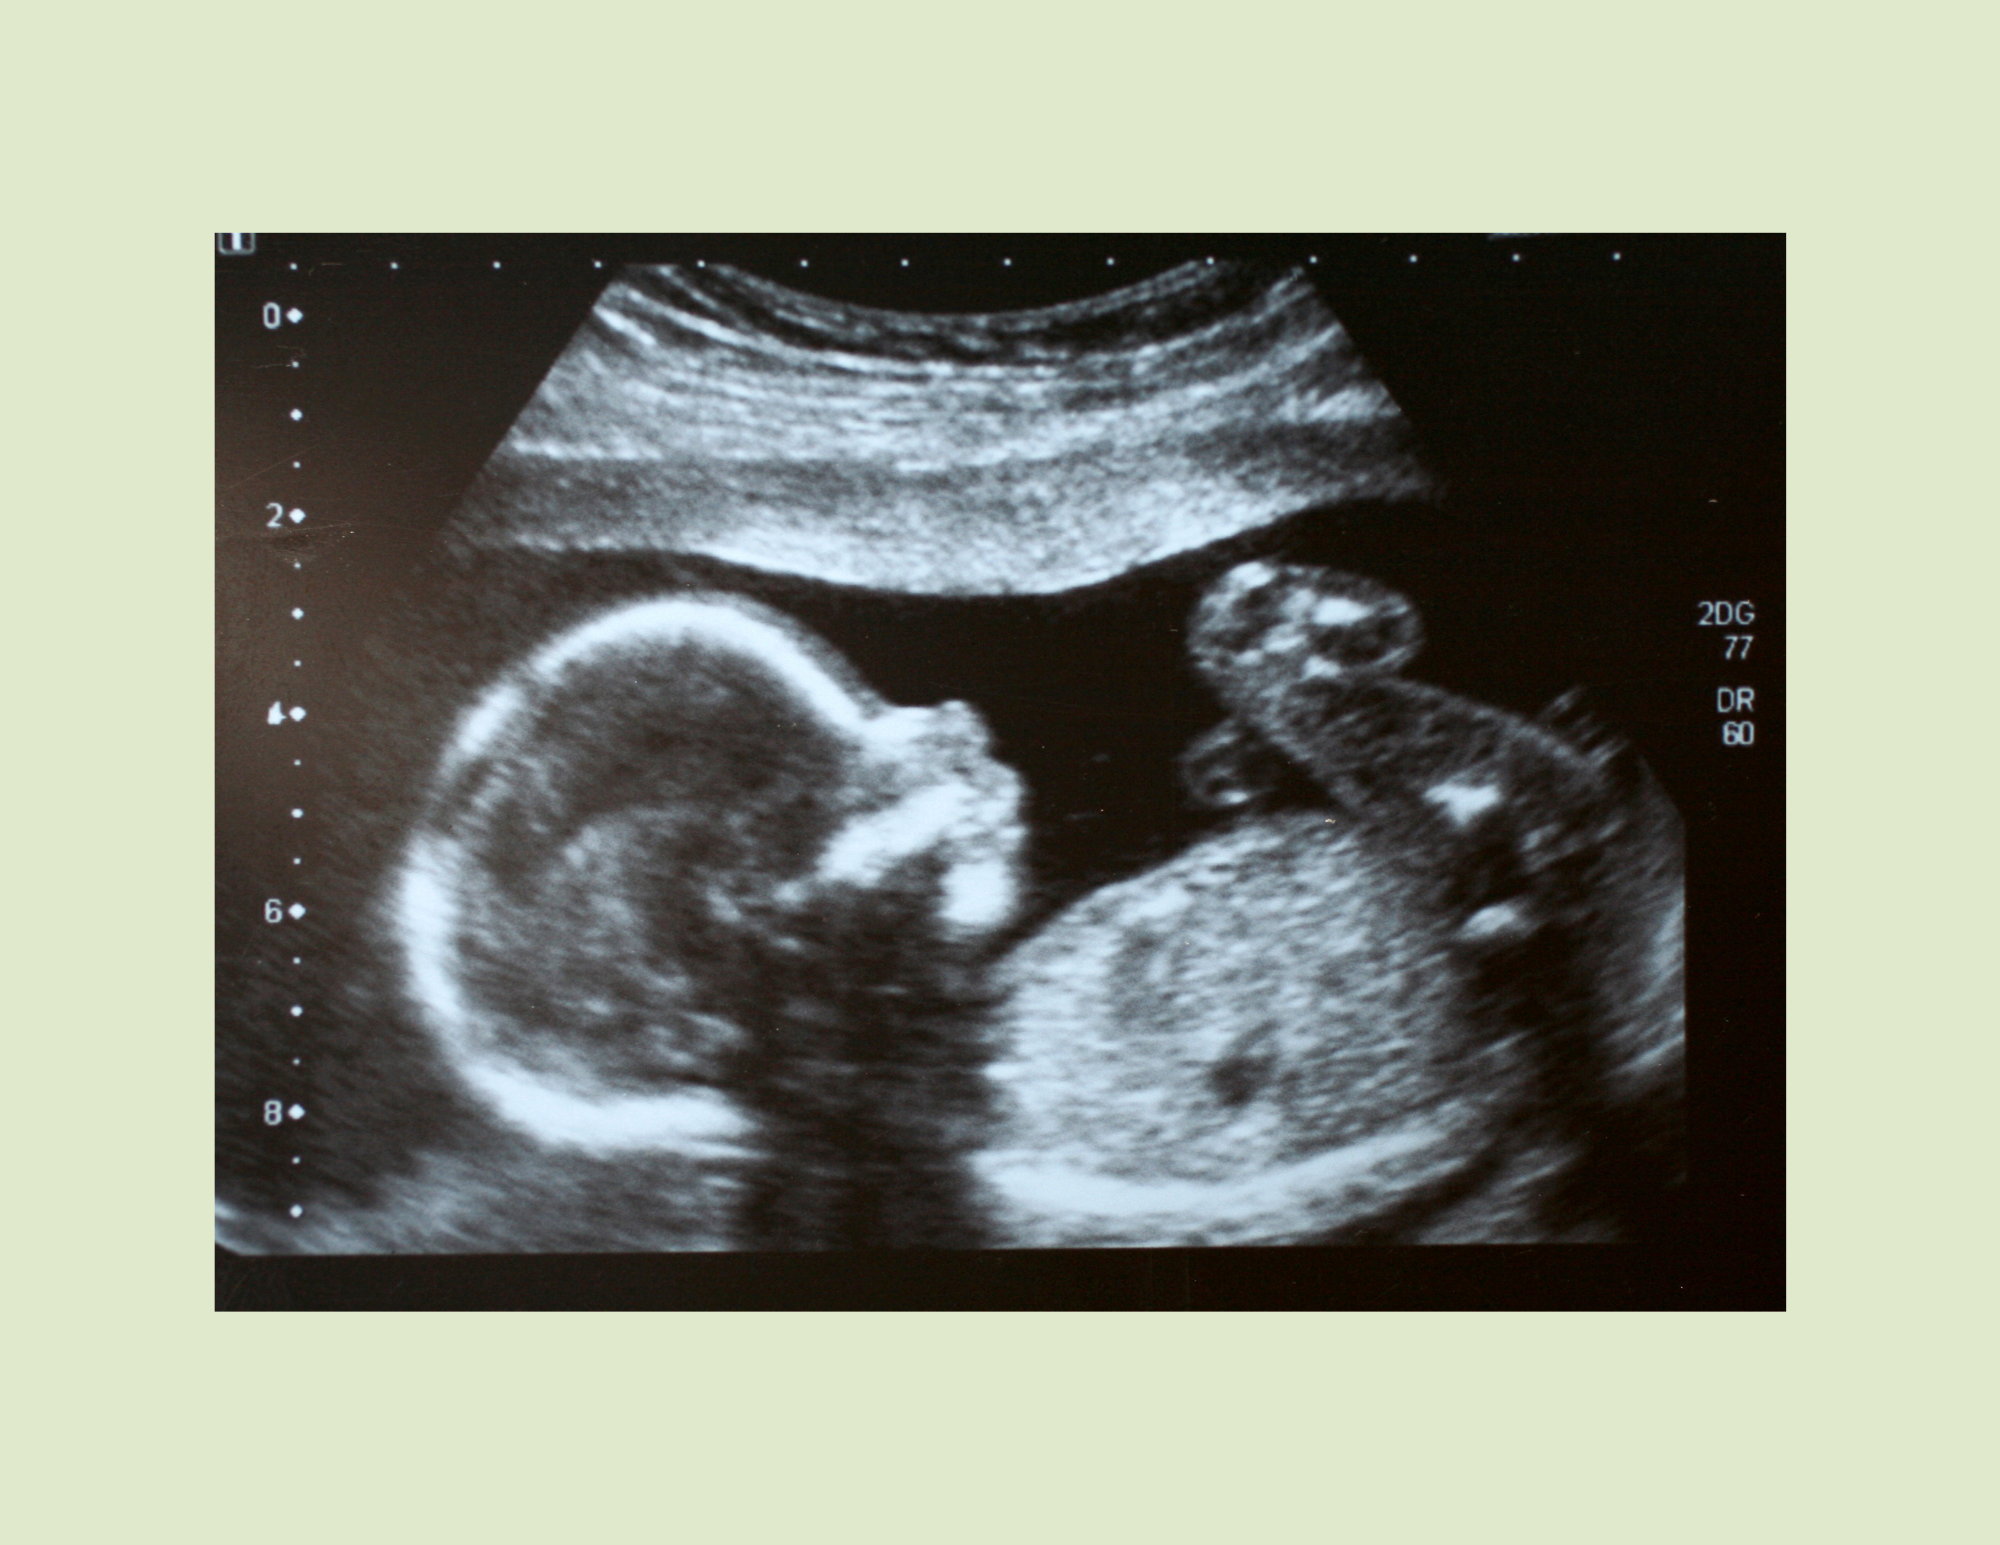

The short answer: sometimes, yes. Your 20-week anatomy scan doesn’t just give you a glimpse of your growing baby—it also provides important information about your placenta, cervix, amniotic fluid, and baby’s growth. These findings can help your healthcare team and your pelvic floor therapist adjust your exercise plan to keep both you and baby safe.

The anatomy scan (usually performed between 18–22 weeks) is designed to check: